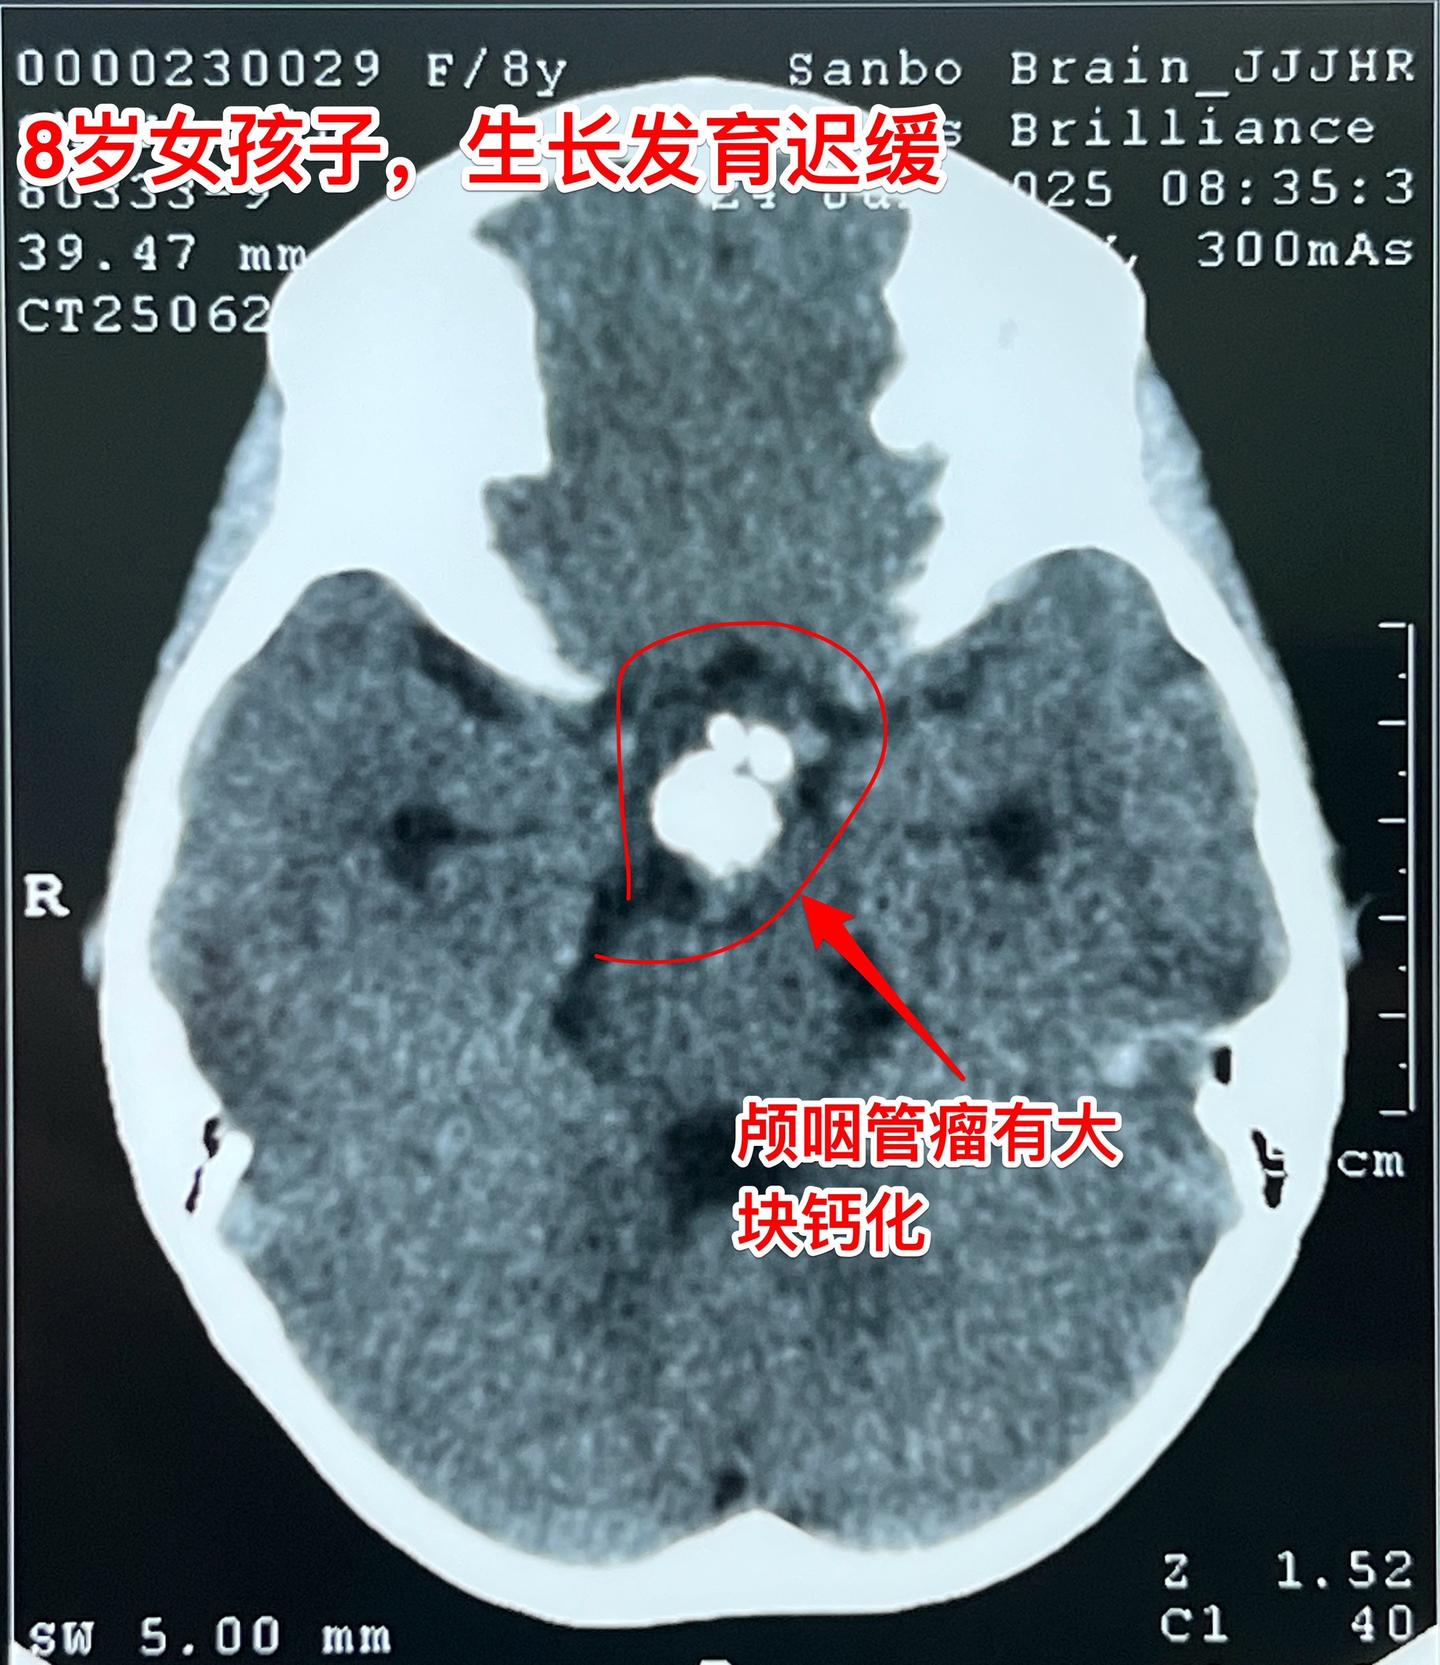

八岁烟台女孩子身高增长缓慢—原因找到了。八岁女孩子,父母都是大高个。近两年女孩子身高增长很缓慢,一开始没有引起重视。随着身高差距拉大,家长重视起来了。 2025年6月到医院检查头部磁共振、CT,一下子就找到原因了:脑部长了颅咽管瘤,这个颅咽管瘤还有一大块钙化。 女孩子除了身高增长缓慢之外,无视力下降,无多饮多尿症状,精神状态也很好。 女孩子的舅舅也是神经外科医生,上周找我看了门诊,他们接受开颅手术。 今天的手术很顺利,颅咽管瘤得到完全切除。